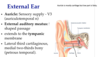

What are these nerves innervated by?

What are these nerves and their function?